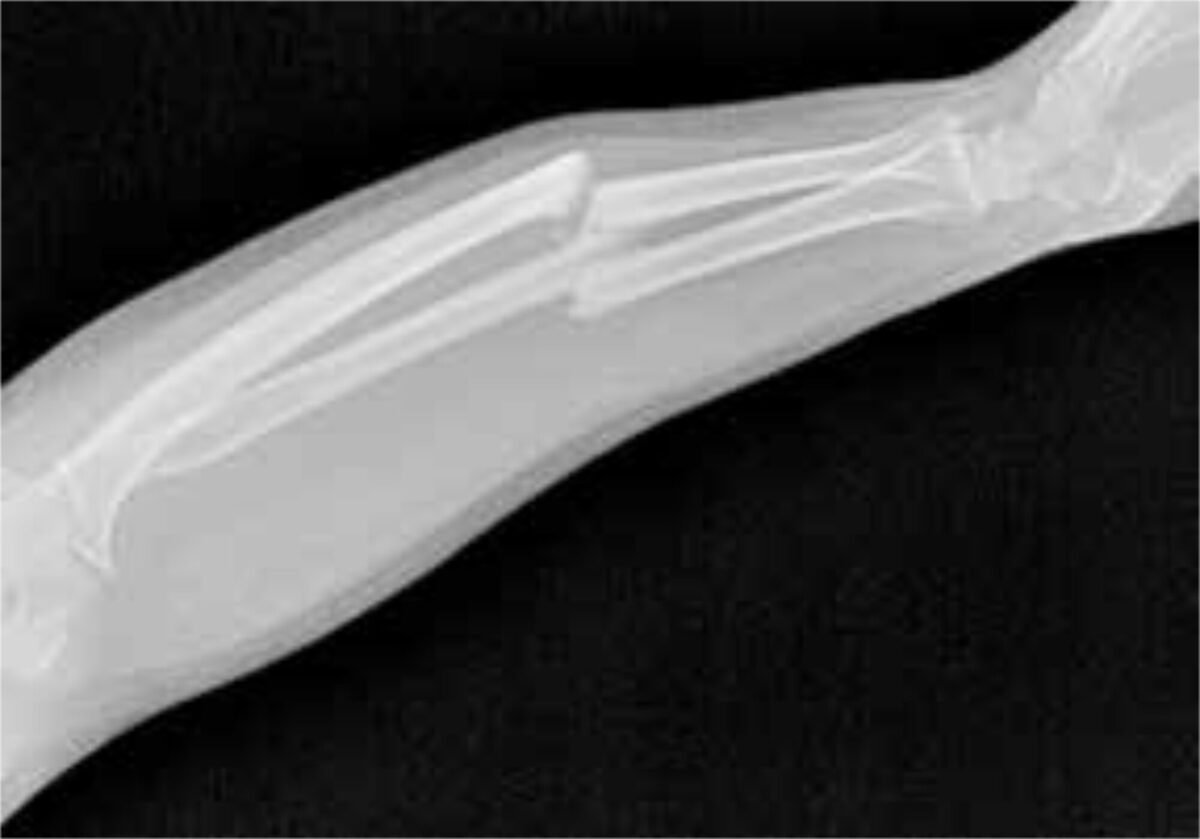

A 29-year-old man presented at the outpatient clinic with a small bandage on his left arm; he had injured his arm three months before in a motorcycle accident. He had first gone to the traditional healer, but after three months there was no significant improvement. Upon clinical examination abnormal mobility was felt midway in his lower left arm. No wounds or scars were observed and his left hand had normal function. The X-ray showed a midshaft fracture of both ulna and radius (figure 1). Initially plaster of Paris (POP) was applied under traction for three weeks to improve position.

The above-mentioned possibilities were discussed with the patient and he preferred to be operated in The Lion Heart Medical centre at short notice. With the help of detailed instructions from the specialists the procedure was carried out. In theatre, the old callus was scraped away from the fracture ends and both the radius and ulna were fixated with metal pins (k-wires). Unfortunately the X-ray (figure 2) showed that the pin through the radius was misplaced and therefore had to be removed immediately after the procedure. POP was applied to the upper and lower left arm for six more weeks, after which the second pin was removed. POP was applied again for three more weeks.